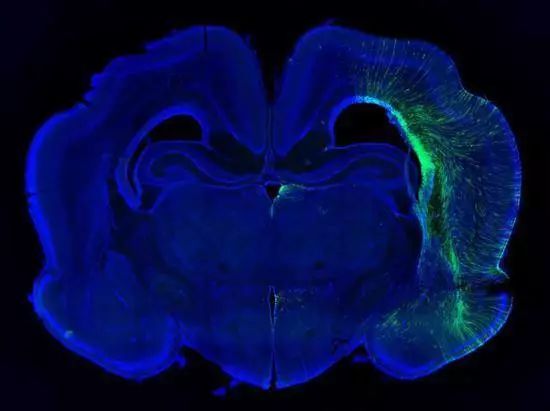

Walsh,Bae的研究團隊發現雪貂與小鼠相比,能更準確地模擬人類小頭畸形。基因敲除後,雪貂出現了嚴重的腦萎縮,大腦減重了40%。並且,與在同一條件下的人類相似,雪貂腦萎縮前後的皮質厚度和細胞結構基本維持不變。

更geng重zhong要yao的de是shi,在zai雪xue貂diao模mo型xing上shang進jin行xing的de研yan究jiu揭jie示shi了le人ren類lei大da腦nao在zai演yan化hua過guo程cheng中zhong一yi種zhong可ke能neng的de生sheng長chang機ji製zhi。在zai過guo去qu的de七qi百bai萬wan年nian裏li,人ren類lei的de大da腦nao體ti積ji增zeng加jia了le三san倍bei。這zhe一yi擴kuo增zeng主zhu要yao發fa生sheng在zai大da腦nao皮pi層ceng上shang。

通過對基因敲除後的雪貂的大腦皮層萎縮進行追蹤觀察,研究人員發現這是由一種外放射狀膠質細胞(ORGs)導致的。ORGs由幹細胞分化產生,具有進一步分化成為皮層中各類細胞的能力。Walsh的團隊發現,ASPM能夠調控幹細胞分化成ORGs的時間點。這將會影響ORGs與其它細胞的比例。Walsh表示,因此無需一次性改變很多基因,對ASPM進行微調便可以增加或減少腦部的神經細胞數量。